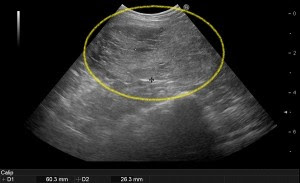

犬の前立腺肥大症に対する酢酸クロルマジノンの治療効果 小嶋佳彦1)川 上静夫2)紫 野正雄2) 1) 小島動物病院(〒956新 津市秋葉) 2) 麻布大学獣医学部(〒229相 模原市渕野辺) (1996年10月14日 受付・1997年8月25日 受理) 要 約 犬の前立腺肥大症例に酢酸クロルマジノン(CMA)錠 剤を連続経口投与 · 犬の前立腺肥大、症状は? 初期はほとんど無症状ですが、肥大がすすむとさまざまな症状がみられるようになります。 前立腺は尿道を囲むように存在することから、尿道が圧迫され、血尿になったり排尿が困難になったりします。また、直腸の下にあるので、直腸が圧迫されることで「便の形が細くなる、平らになる」などの排便異常や便秘、排便困難といった症状前立腺肥大犬のXray 正常犬のXray 前立腺肥大犬のエコー画像 ・症状 前立腺の肥大により骨盤腔内の臓器(主に直腸や尿道)が圧迫され、排便困難や排尿困難、尿失禁を引き起こします。 ・診断 直腸内触診、レントゲン、エコー検査により肥大した前立腺を確認できます。 ・治療方法 内科